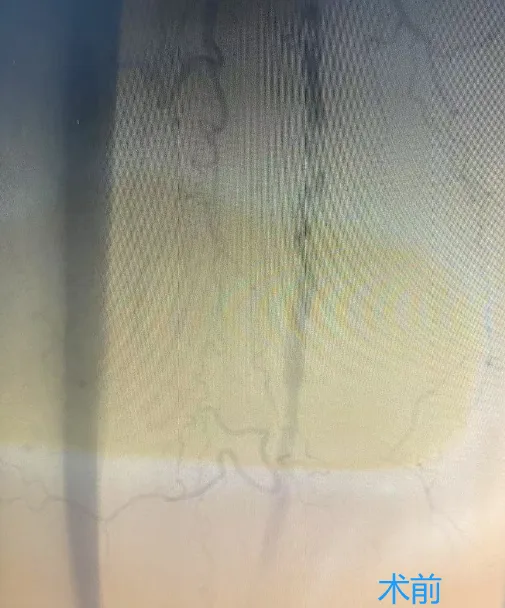

下肢動脈硬化閉塞癥的治療方式包括:生活方式調整、藥物治療、血管腔內治療、外科手術和康復等方法,可有效緩解癥狀,提升生活質量。特別是下肢動脈旋切術,作為微創(chuàng)技術,能有效清除血管壁上的斑塊。

下肢動脈旋切術的優(yōu)勢

圖片

1、無需植入支架降低了遠期并發(fā)癥的發(fā)生率,如血栓和再狹窄等。

2、創(chuàng)傷小,恢復快:減輕了手術痛苦,加速了術后恢復,使患者能迅速回歸日常生活。

3、治療效果顯著:改善下肢動脈閉塞,恢復血流暢通,緩解疼痛,提高生活質量。

葫蘆島市第二人民醫(yī)院血管介入病區(qū)現(xiàn)已常規(guī)開展下肢動脈旋切術,標志著我市周圍血管疾病微創(chuàng)技術及相關領域診療水平邁上了新臺階。這一技術的廣泛應用,結合先進的影像技術,將為更多下肢動脈疾病患者帶來福音,讓他們重獲健康與希望。